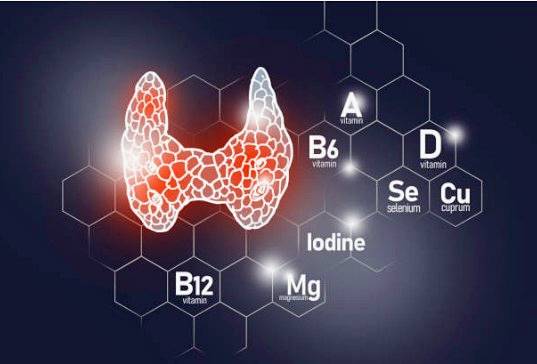

적절한 갑상샘 호르몬 분비를 인체의 신체 활동을 원활하게 하고 체온을 유지하는 등 역할을 하는 데 중요한 호르몬이 된다.

갑상샘에서는 갑상샘호르몬 분비가 일어나는데 적을 때는 갑상샘저하증, 많을 때는 반대로 항진증이라는 개념으로 보면 되며 이는 많아도 문제, 적어도 문제이므로 균형이 잘 잡힌 호르몬 분비가 가장 좋다.